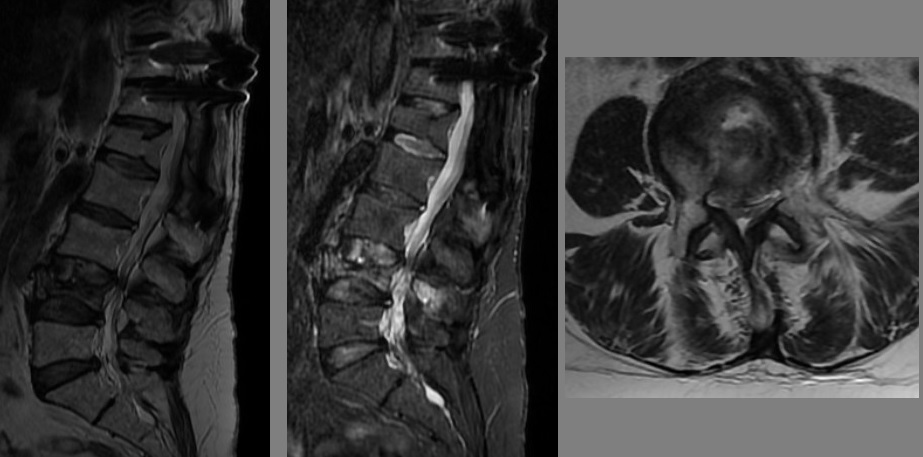

MRG

incelemelerinde L4 vertebrasında akut/subakut dönemde patlama kırığı ve

bu seviyede belirgin kanal daralması izlenmekte.